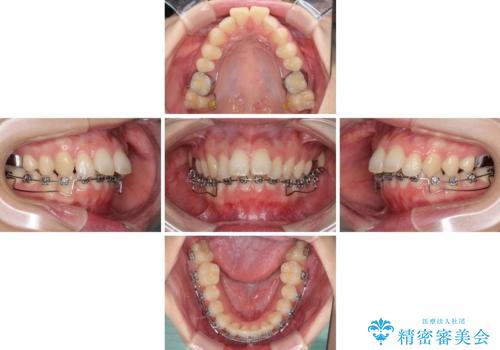

- メタルブラケット

- 3年1ヶ月

- 口元の突出感を気にして来院された患者様です。

左右ともに上顎奥歯が外を向き、下顎奥歯が内側に倒れているシザーズバイトであったため、補助装置により改善することとしました。

上下の咬み合わせは、下顎に対して上顎が相対的に前方にあったため、奥歯のシザーズバイト改善後に上顎左右第一小臼歯2本を抜歯し、上顎前突を改善していくこととしました。

左側の咬み合わせと上下正中の位置をコントロールするために時間がかかりましたが、事前に思い描いた通りの歯列に整い、患者様には大変満足していただきました。